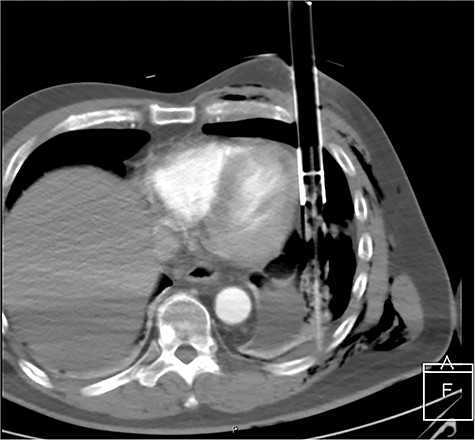

After primary survey and usual trauma imaging showed no air of fluid in either hemithorax, the patient underwent an emergent computed tomography (CT), which revealed a metal pole traversing the left hemithorax penetrating to the posterior chest wall at the level of the ninth rib. The metal pole was abutting the pericardium and was touching the posterior chest wall (Figs 1, 2 and 3).

CT axial view of penetrating solar powered garden light demonstrating proximity of metal shaft to heart and the plastic tip resting against the posterior thorax.